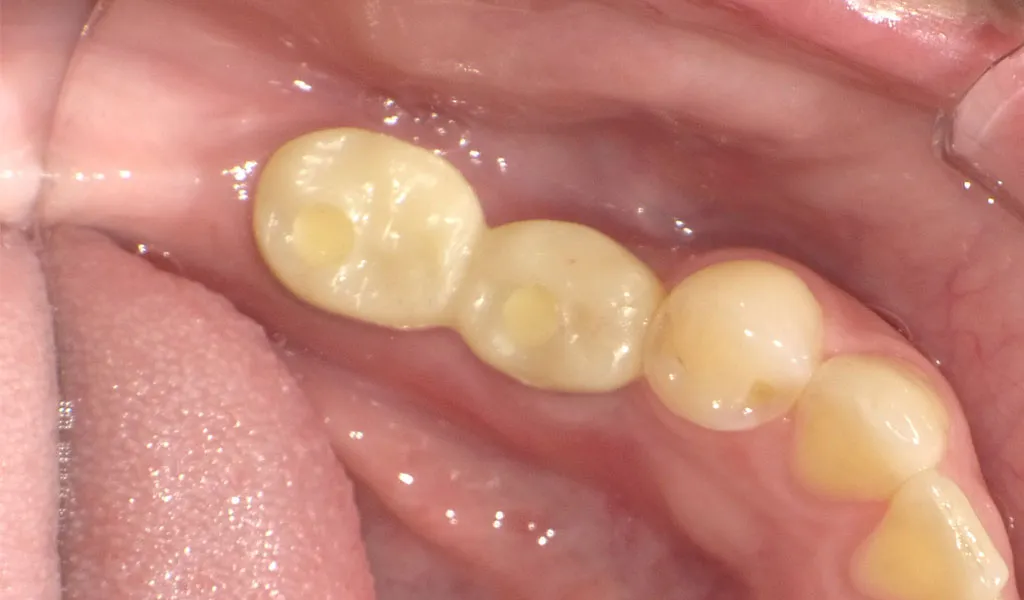

Before

After

奥歯2本のインプラント治療

30代女性

治療期間:4ヶ月

費用:総額64.9万円(検査・診断・手術関連処置費用等を含む)

リスク:出血、腫脹、疼痛、神経麻痺、補綴物の脱落、破折、インプラント体の破折、咬合違和感、インプラント周囲炎など -